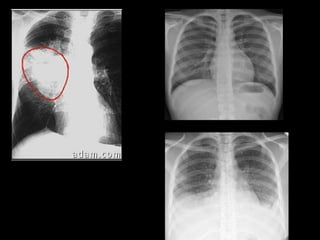

Imagens de radiografias

Exame Dose  Raio X Tórax 0,03 mSv TC cabeça 2 mSv TC abdomen 10 mSv Urografia 4 mSv Intervenção 1 – 100 mSV